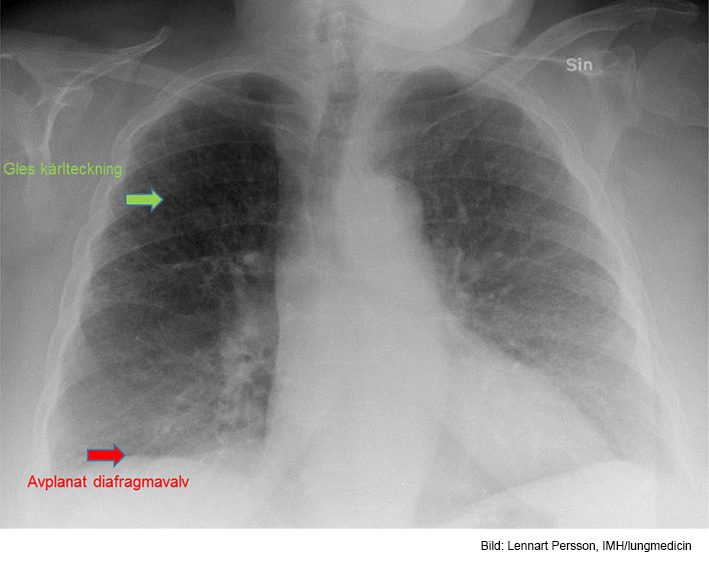

Vad visar röntgen?

Bild förenlig med t ex KOL

Gles kärlteckning, särskilt apikalt (emfysem ev) och antytt avplanade diafragmakupoler, särskilt höger, förenligt med KOL. Något förstorat hjärta men ingen stas.

Litet infiltrat basalt höger